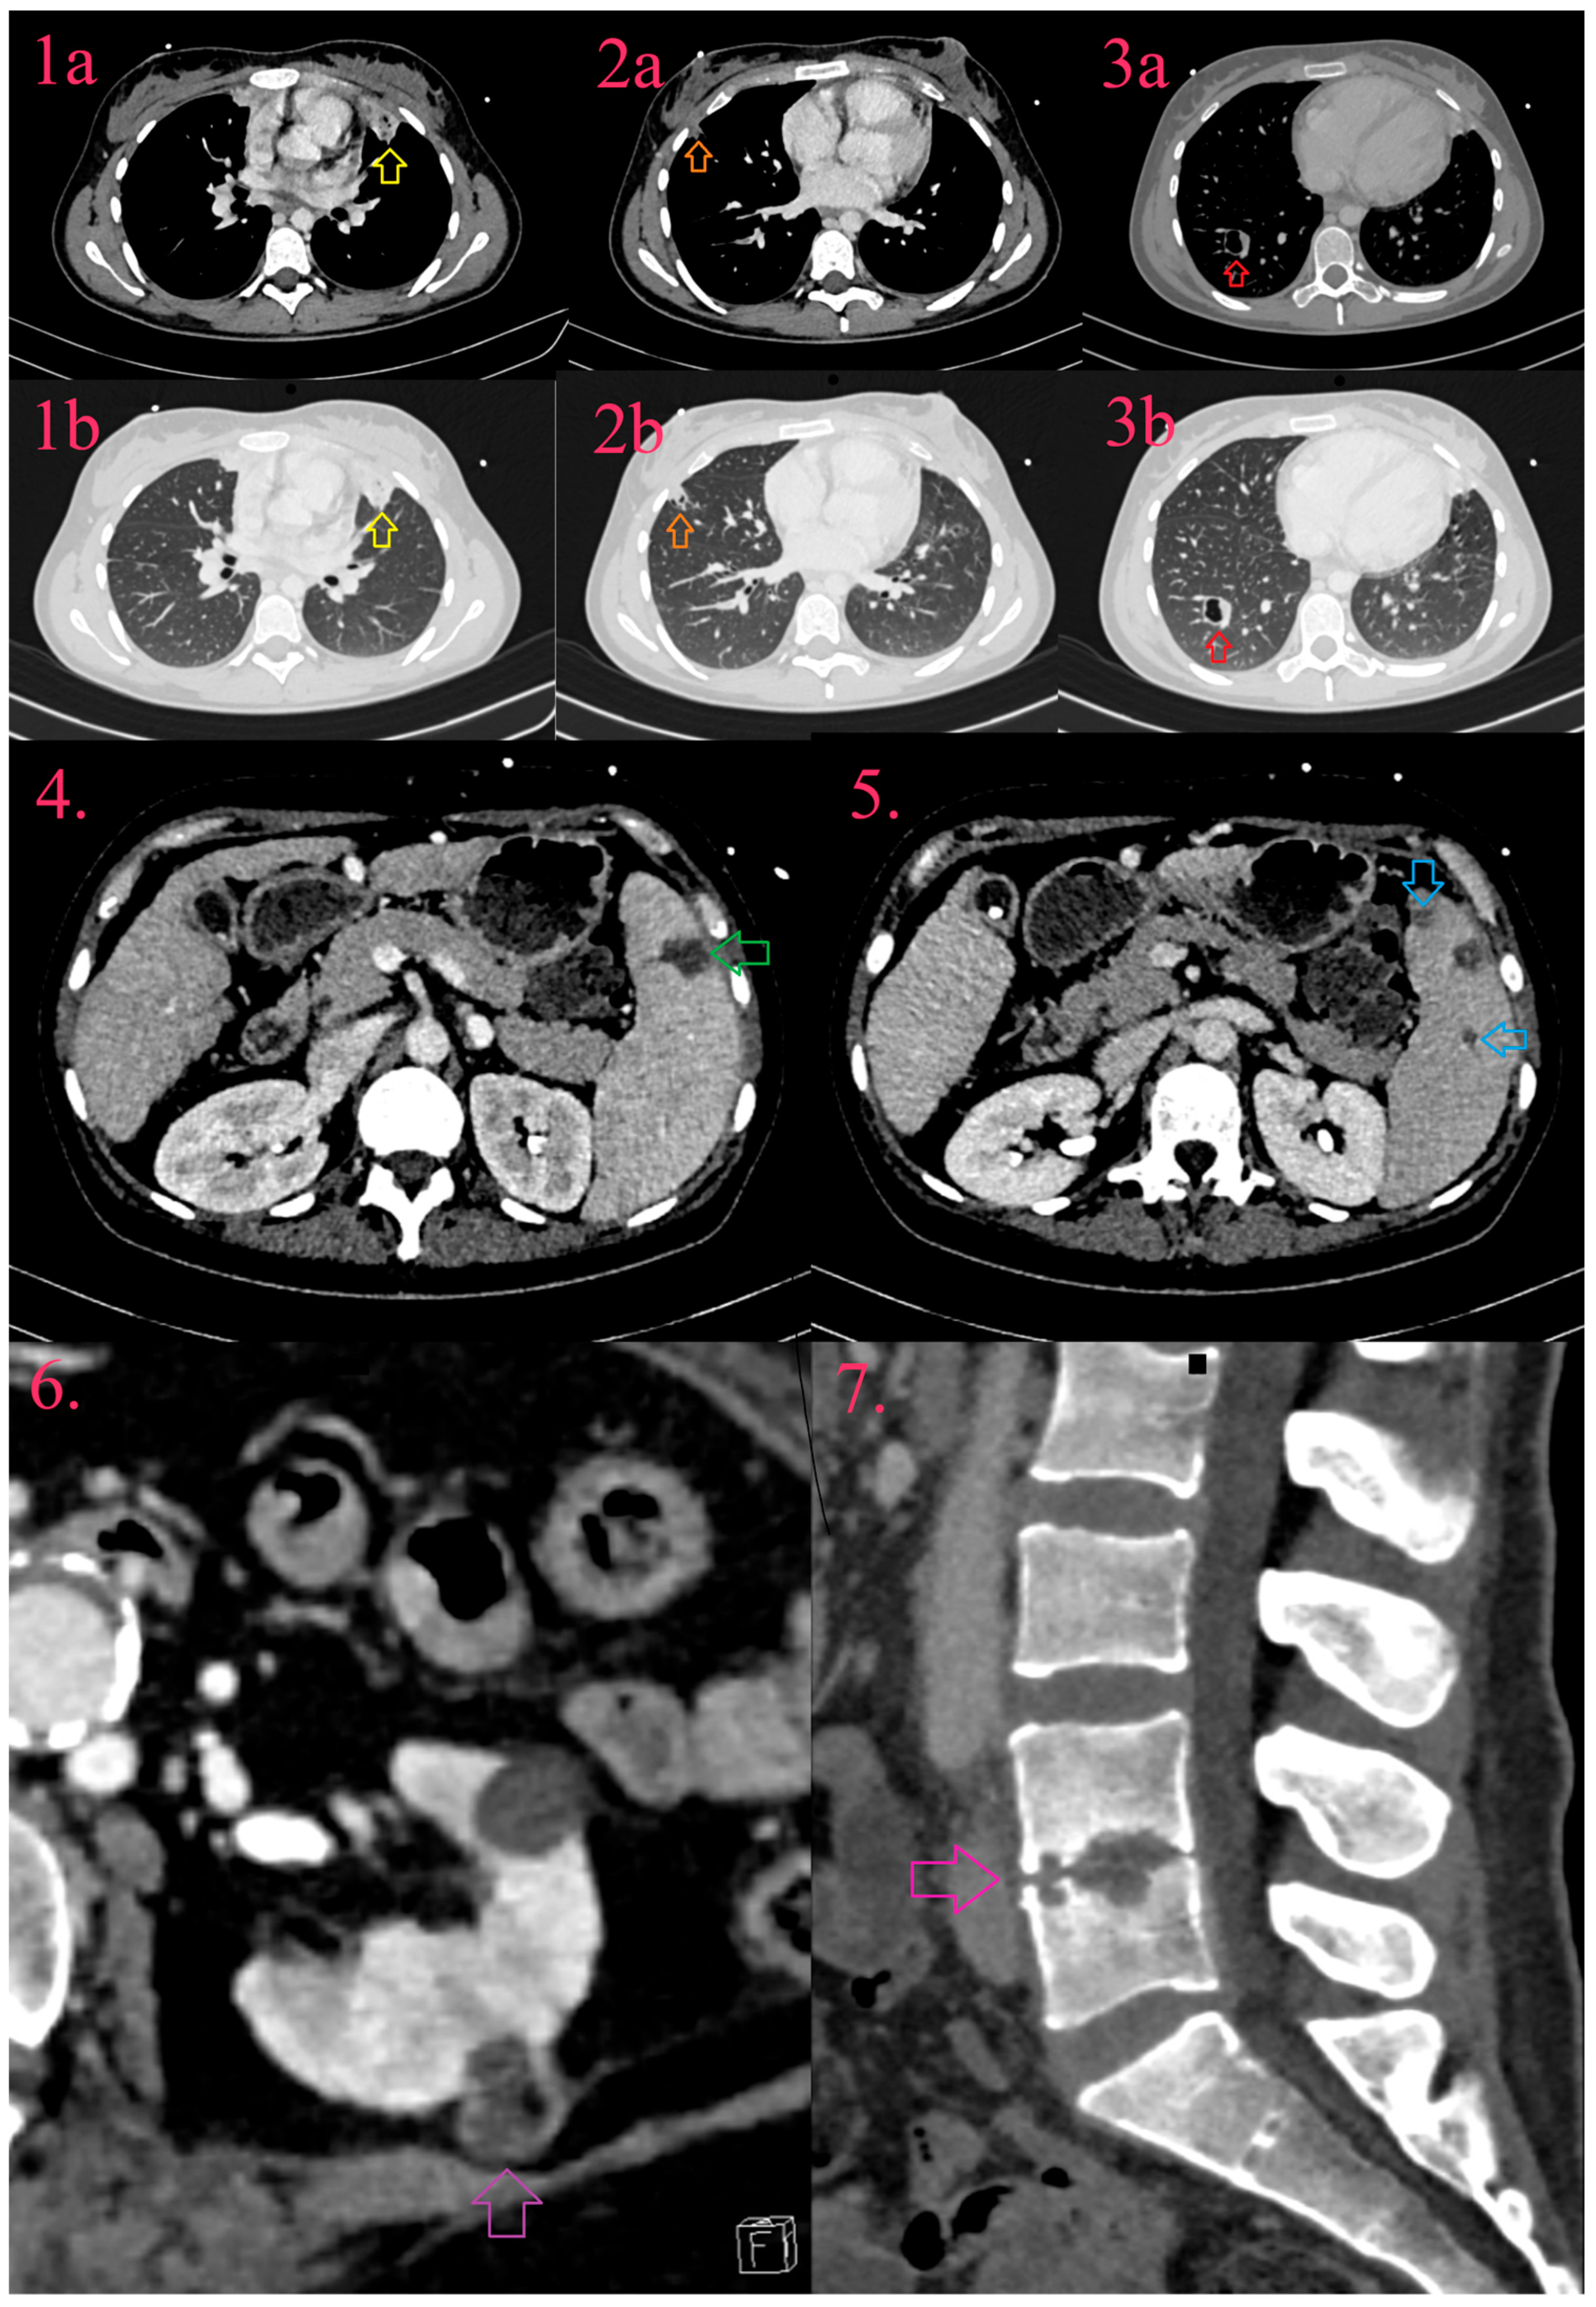

There are almost exclusively consequences of right-sided IE and they occur in 14% of patients with IE with systemic embolism. They include pulmonary infarction, pulmonary abscess, pleural effusion, and empyema (Figure 6, Images 1a,b, Images 2a,b and Images 3a,b) [19,32].

Figure 6.

Systemic dissemination of infective endocarditis. Multiple lung abscesses in form of consolidation (Image 1a and 1b, yellow arrow), partial cavitation (Image 2a and Image 2b, orange arrow), and cavitation with fluid level (Image 3a and Image 3b, red arrow). Spleen abscess (Image 4, green arrow) and two infarcts (Image 5, blue arrow). Abscess of left kidney (Image 6, purple arrow). Spondylodiscitis with loss of intervertebral space and erosion of end-plates of vertebral bodies L4 and L5 (Image 7, pink arrow).

11.4. Abdominal Complications

Abdominal complications are associated with left-sided infective endocarditis, with the spleen as the most often affected organ (19–32%), following the kidneys (6–14%), and rarely the liver (3–11%) [76]. Splenic involvement includes asymptomatic infarction, with progression to abscess and potential rupture (Figure 6, Image 4 and Image 5) [19]. The kidney follows the same development pattern as in the spleen; infarcts progress to abscesses and are often multiple, sometimes bilateral (Figure 6, Image 6). Liver involvement is manifested by abscess. CT depicts infarct, independent of the affected organ, as triangular hypodense lesion, which with the development of contrast-enhanced peripheral rim, develops into abscess, that may strain the organ capsule [32].

11.5. Musculoskeletal Complications

Metastatic bone or joint-IE related lesions are relatively frequent, and include spondylodiscitis (2–10%), osteomyelitis, and septic arthritis. MRI is a preferable imaging modality in comparison to CT. In spondylodiscitis, CT detects indirect signs of disease such as loss of disc height, erosion or destruction of end-plates and vertebral bodies, and paravertebral soft tissue collections with abscess development (Figure 6, Image 7) [19,32].